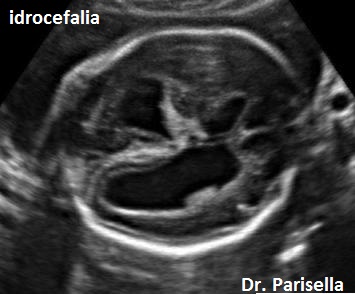

E' una patologia rara caratterizzata da craniosinostosi delle suture coronale e lambdoidea con conseguente brachicefalia, anomalie facciali ( bozze frontali prominenti, ipoplasia medio-facciale, proptosi), anomalie scheletriche (sinostosi radio-omerale, femore curvo, ulna curva, contratture articolari, campodattilia), anomalie del SNC (Idrocefalia), cardiopatie congenite (DIA), anomalie renali, anomalie dell'apparato genito-urinario (atresia vaginale, ipoplasia grandi labbra, fusione piccole labbra). I gomiti sono fissi causa la sinostosi radio-omerale.